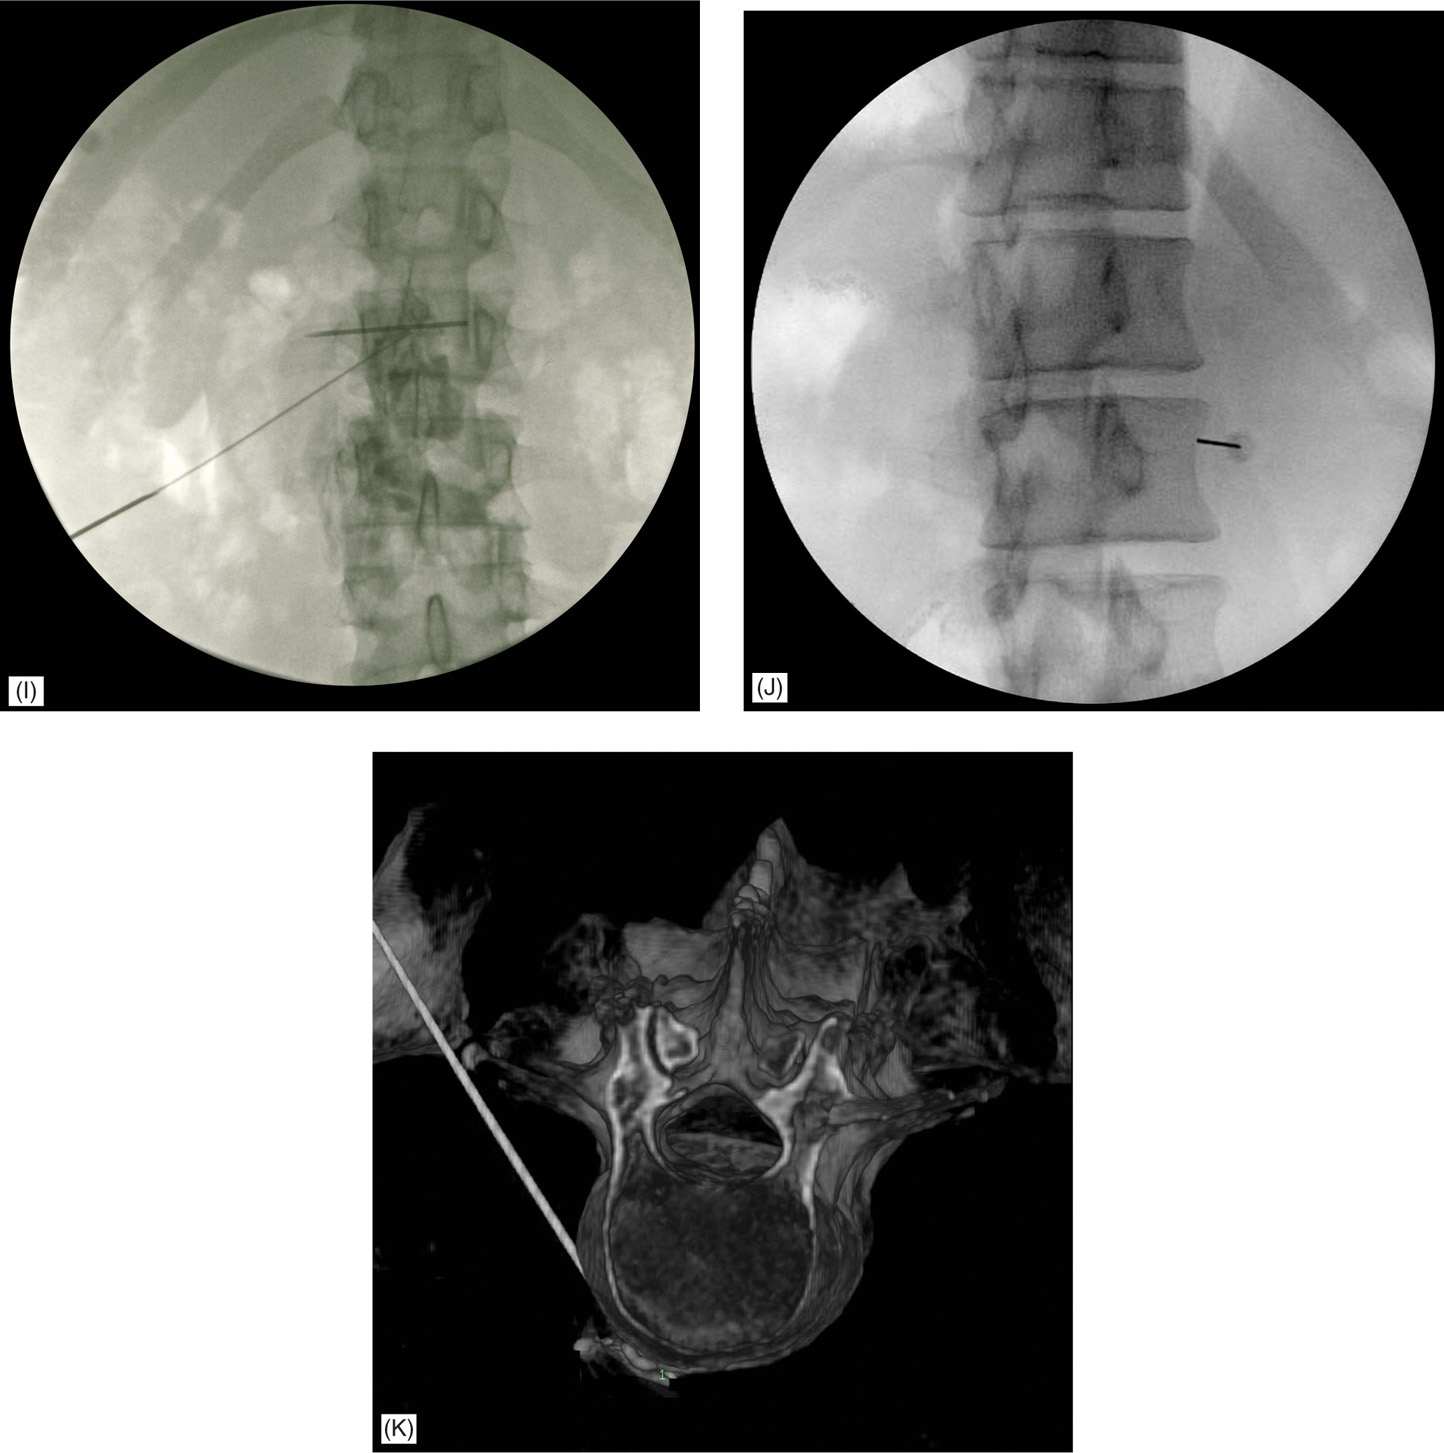

From www.orthoracle.com

Lumbar nerve root block Surgical Technique OrthOracle Lumbar Hardware Block Cpt Let’s delve into the world of coding and its significance in the context of spinal block surgeries. Examples of the appropriate use of code 64450 include the nerve block of the sensory posterior articular nerves of the knee (spank block) or a. When an individual experiences chronic pain it is. This article provides guidance on how to bill and code. Lumbar Hardware Block Cpt.